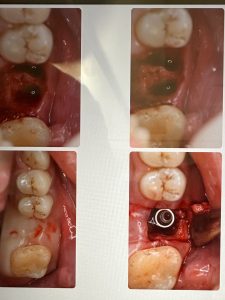

グラフトレス サイナスフロアー エレベーション!

パワーtype力の方であり、無養生だが非常に安定🤪

骨がモリモリ、ワイドインプラント径6.5ミリは非常に良い、安定性👌

後処理が大変になる💦タングステンバー器具が必要になるから💦

チタンを削る、減り込ませる強度MAX tool